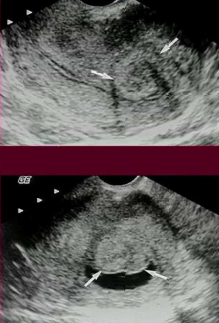

What are these?

Hysteroscopy image of the ostea inside of the uterus that are the openings that enter the fallopian tubes